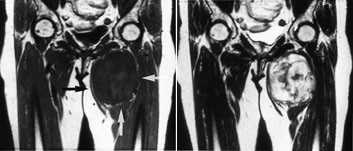

Bløtvevssvulster

Konvensjonelle røntgenbilder er første trinn i utredningen av mistenkte bløtvevssvulster (12). De viser underliggende skjelettdeformitet, beinaffeksjon og bløtvevsforkalkninger. Forkalkninger kan ikke påvises med MR. MR er allikevel den beste metoden, fordi den i tillegg til å vise de anatomiske forhold også fremstiller væske, nekrose, blødning, fett og annet bløtvev (fig 6 – 8). Basert på vekstmønster og signalforhold kan vevsspesifikk diagnose stilles i 20 – 40 % av tilfellene. Det er oftest ikke mulig å angi om en bløtvevstumor er benign eller malign. Nekrose er den enkeltfaktor som sterkest peker i retning av malignitet. Andre faresignaler er stor tumor, uskarp avgrensning med omgivende ødem, heterogent signal og beinaffeksjon. Men høymaligne bløtvevssvulster kan være velavgrenset med en pseudokapsel.